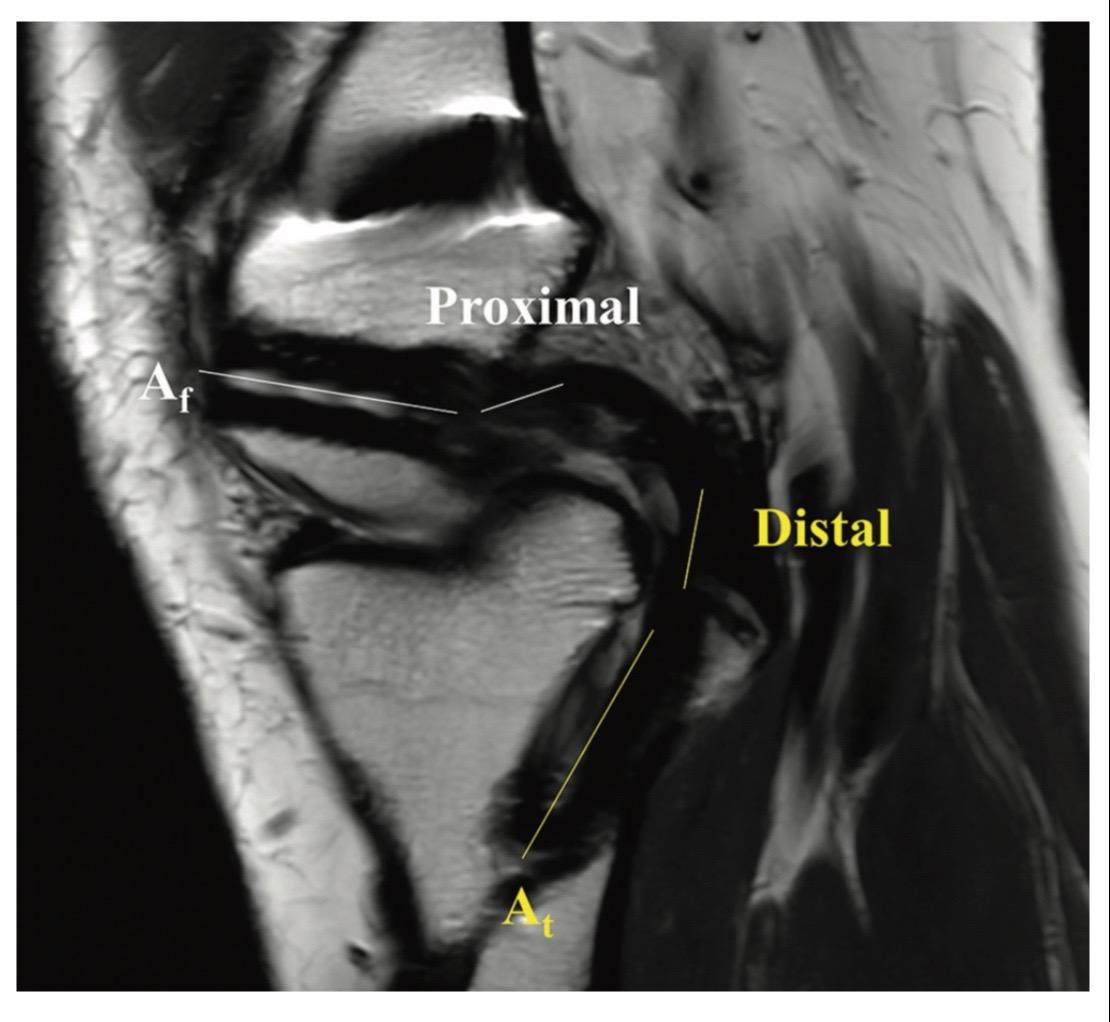

后交叉韧带重建。后交叉韧带(PCL)重建手术中,适当的隧道位置、隧道角度和移植物角度对于维持PCL移植物的稳定性和机械性能至关重要!